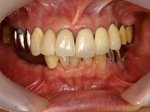

術後口腔内(正面観)もう入れ歯は要らなくなりました。